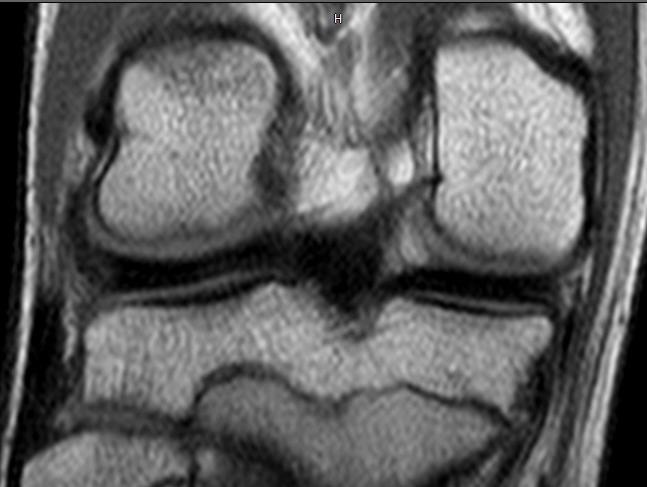

Երեխան, ով ակտիվ զբաղվում է պրոֆեսիոնալ ֆուտբոլով, վնասվածք էր ստացել ծնկան հոդում: Ծնողները դիմել էին բժշկական կենտրոններից մեկի մասնագետներին, սակայն նրանք չէին կարողացել ախտորոշել վնասվածքը՝առաջարկելով զուտ ռեաբիլիտացիոն բուժում և ներհոդային հորմոնալ պրեպարատների ներարկում: Սա բավականին տարածված սխալ մոտեցում է, որը ցավոք ընդունված պրակտիկա է Հայաստանում:

Միայն Վնասվածքաբանության և օրթոպեդիայի գիտական կենտրոնի Մանկական վնասվածքաբանության և օրթոպեդիայի բաժանմունքում կատարված հետազոտության ընթացքում ի վերջո կլինիկորեն ախտորոշվել է միջային մահիկի վնասումը, որը հաստատվել է նաև մագինսառեսոնանսային հետազոտության ընթացքում:

ԱՐԴՅՈՒՆՔ . Կատարված արթրոսկոպիկ վիրահատությունը հիվանդին թույլ կտա ՇԱՐՈՒՆԱԿԵԼ ԶԲԱՂՎԵԼ պրոֆեսիոնալ ֆուտբոլով, քանի որ վնասվածքը հայտնաբերված է ժամանակին, բուժված է ադեկվատ կերպով և հետևաբար կարճ ժամանակում ծնկան հոդի ֆունկցիան լիովին կվերականգնվի:

Ի՞ՆՉ ԿԼԻՆԵՐ ԲԱՐՁԻԹՈՂԻ ՎԻՃԱԿՈՒՄ.Ցավոք մենք ունենում ենք բազմաթիվ դեպքեր, երբ ծնկան հոդի վնասվածքների ժամանանակից ադեկվատ բուժման բացակայության պատճառով երեխաները ընդմիշտ հրաժեշտ են տալիս սպորտին, իսկ որոշ դեպքերում պոկված էլեմենտները շարունակում են վնասել ներհոդային աճառը, որը իր հերթին հանդիսանում է ծնկան հոդի արթրոզի ամենահաճախ հանդիպող պատճառը:

. Ի տարբերություն մեծահասակների, երեխայի մոտ ժամանակին կատարված ախտորոշման և վիրահատական միջամտության շնորհիվ կարելի է ոչ թե հեռացնել, այլ վերականգնել վնասված հյուսվածքը, ոը թույլ կտա ամբողջովին վերականգնել հյուսվածքի ֆունկցիան: Ու մեր կլինիկայում այսօր մենք այդ միջամտությունները կատարում ենք նվազ ինվազիվ ու շատ արդյունավետ արթրոսկոպիկ եղանակով:

.բոլոր այն դեպքերում, երբ առկա է ծնկան հոդի վնասում, որն ուղեկցվում է հեմատոմայով, այսինքն կա ներհոդային արյունազեղում, պետք է պարտադիր փնտրել հոդի ներսում որևէ ?բաղադրիչի վնասում, քանի որ ուշացած կամ սխալ գործողությունների արդյունքում հետագայում շատ դժվար է լիովին վերականգնել ծնկան հոդի նորմալ անատոմիան և ֆունկցիան: Իսկ դեպքերի մեծամասնության պարագայում փոքր վնասվածքը ժամանակի ընթացքում ոչ միայն մեծանում է, այլ նաև բերում է ծնկան հոդի այլ ստրուկտուրաների վնասման: Հենց այս պատճառով շատ կարևոր է, որ հետտրավմատիկ ծնկան հոդի արթրոզների ախտորոշումը և բուժումը ծնկան հոդի մասով իրականացվի նեղ մասնագիտացում ստացած օրթոպեդների և ոչ թե այլ մասնագետների կողմից: